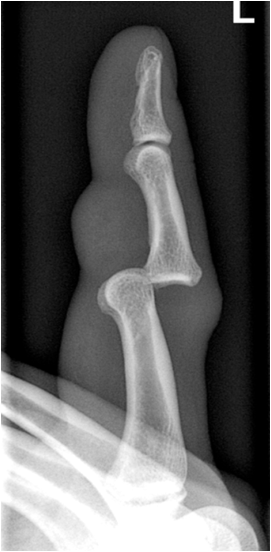

Fig. 2. Images showing a dislocation of the proximal interphalangeal joint. In the d.v.-projection only a slight sideways displacement of the middle phalanx and missing delineation of the joint space is noted. The lateral projection reveals the full extent of the dislocation showing dorsal displacement of the middle phalanx.

Since x-ray films are projection images of three-dimensional structure a second imaging plane, usually perpendicular to the initial exposure is mandatory to fully assess the three-dimensional structure. In complex anatomic regions additional oblique projections or function tests may be necessary (head of radius, shoulder, pelvis, spine).